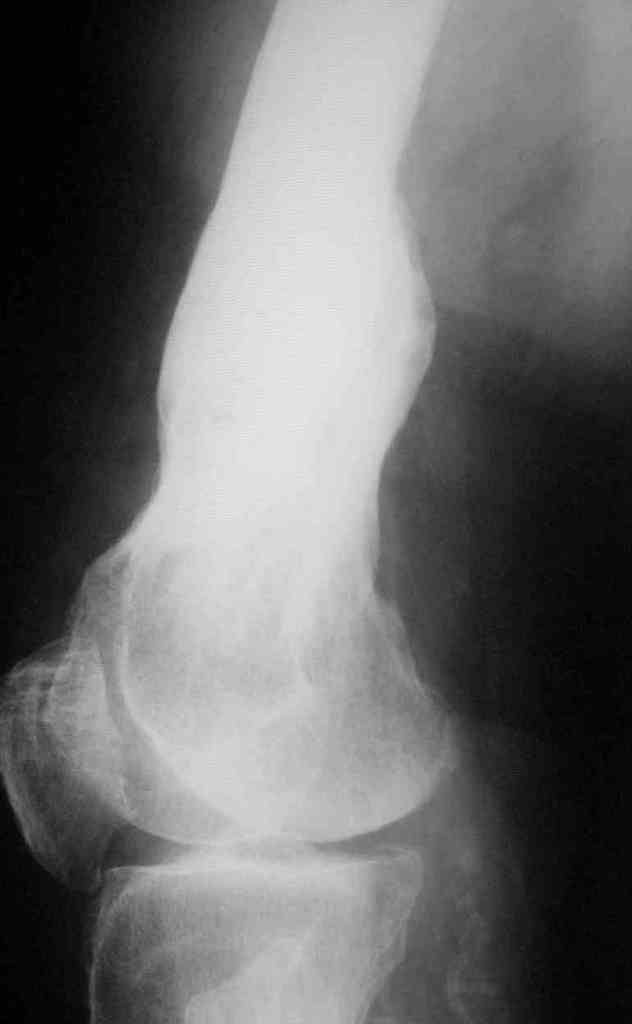

Уважаемые коллеги! Прошу вас принят участие в корректировке алгоритма

действий.

Пациент 69 лет. лечился по поводу перелома н/3 левого бедрамного лет

назад: несостоятельность внутреннего синтеза - АВф- хр. остеомиелит,

свищевая форма с периодическими рецидивами. Результат - укорочение

левого бедра 8 см.

В приложении рентгенограммы и внешний вид бедра.